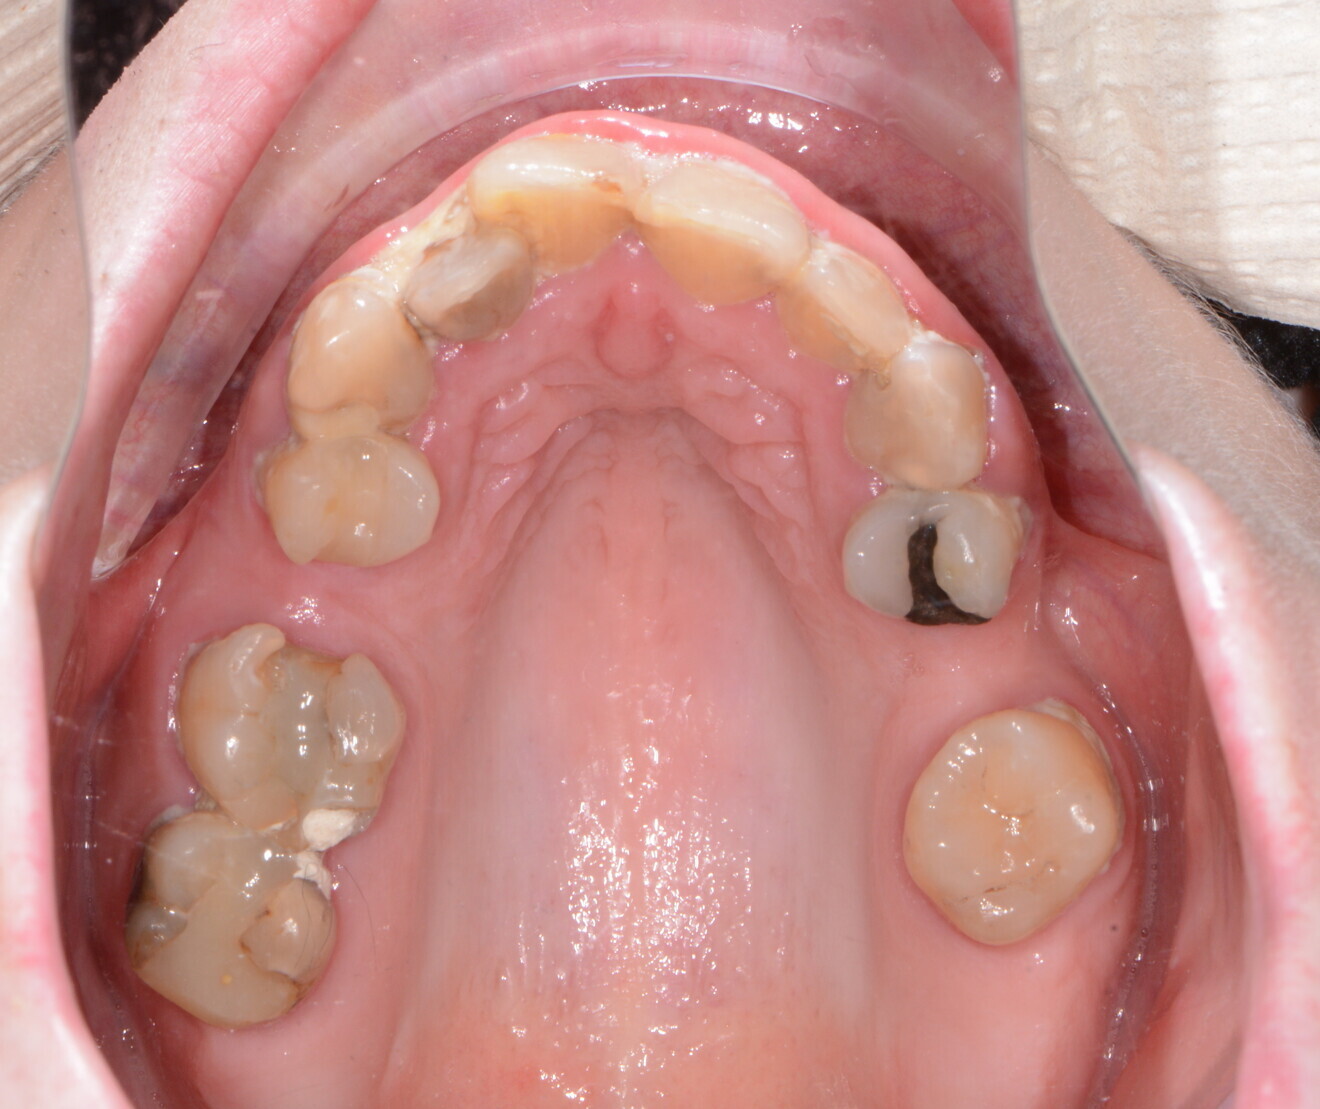

A patient presented to my practice for a consultation, wanting to restore her maxillary dentition to proper form and function (Figs. 1 & 2). She complained of generalised discomfort in these maxillary teeth apparently due to advanced decay as well as periodontal disease. Although her mandibular dentition would require definitive treatment in the future, the patient wanted to focus on her maxillary teeth at that time.

The clinical evaluation included gathering information regarding lip length and support at rest and at smiling, existing position of the natural teeth, occlusion and restorative space. In addition, digital images of the frontal, side and occlusal views of the dentition, as well as complete facial shots, were captured with a Nikon D7200 (PhotoMed).

Fig. 1: Pre-op retracted frontal view.

Fig. 2: Pre-op occlusal view.